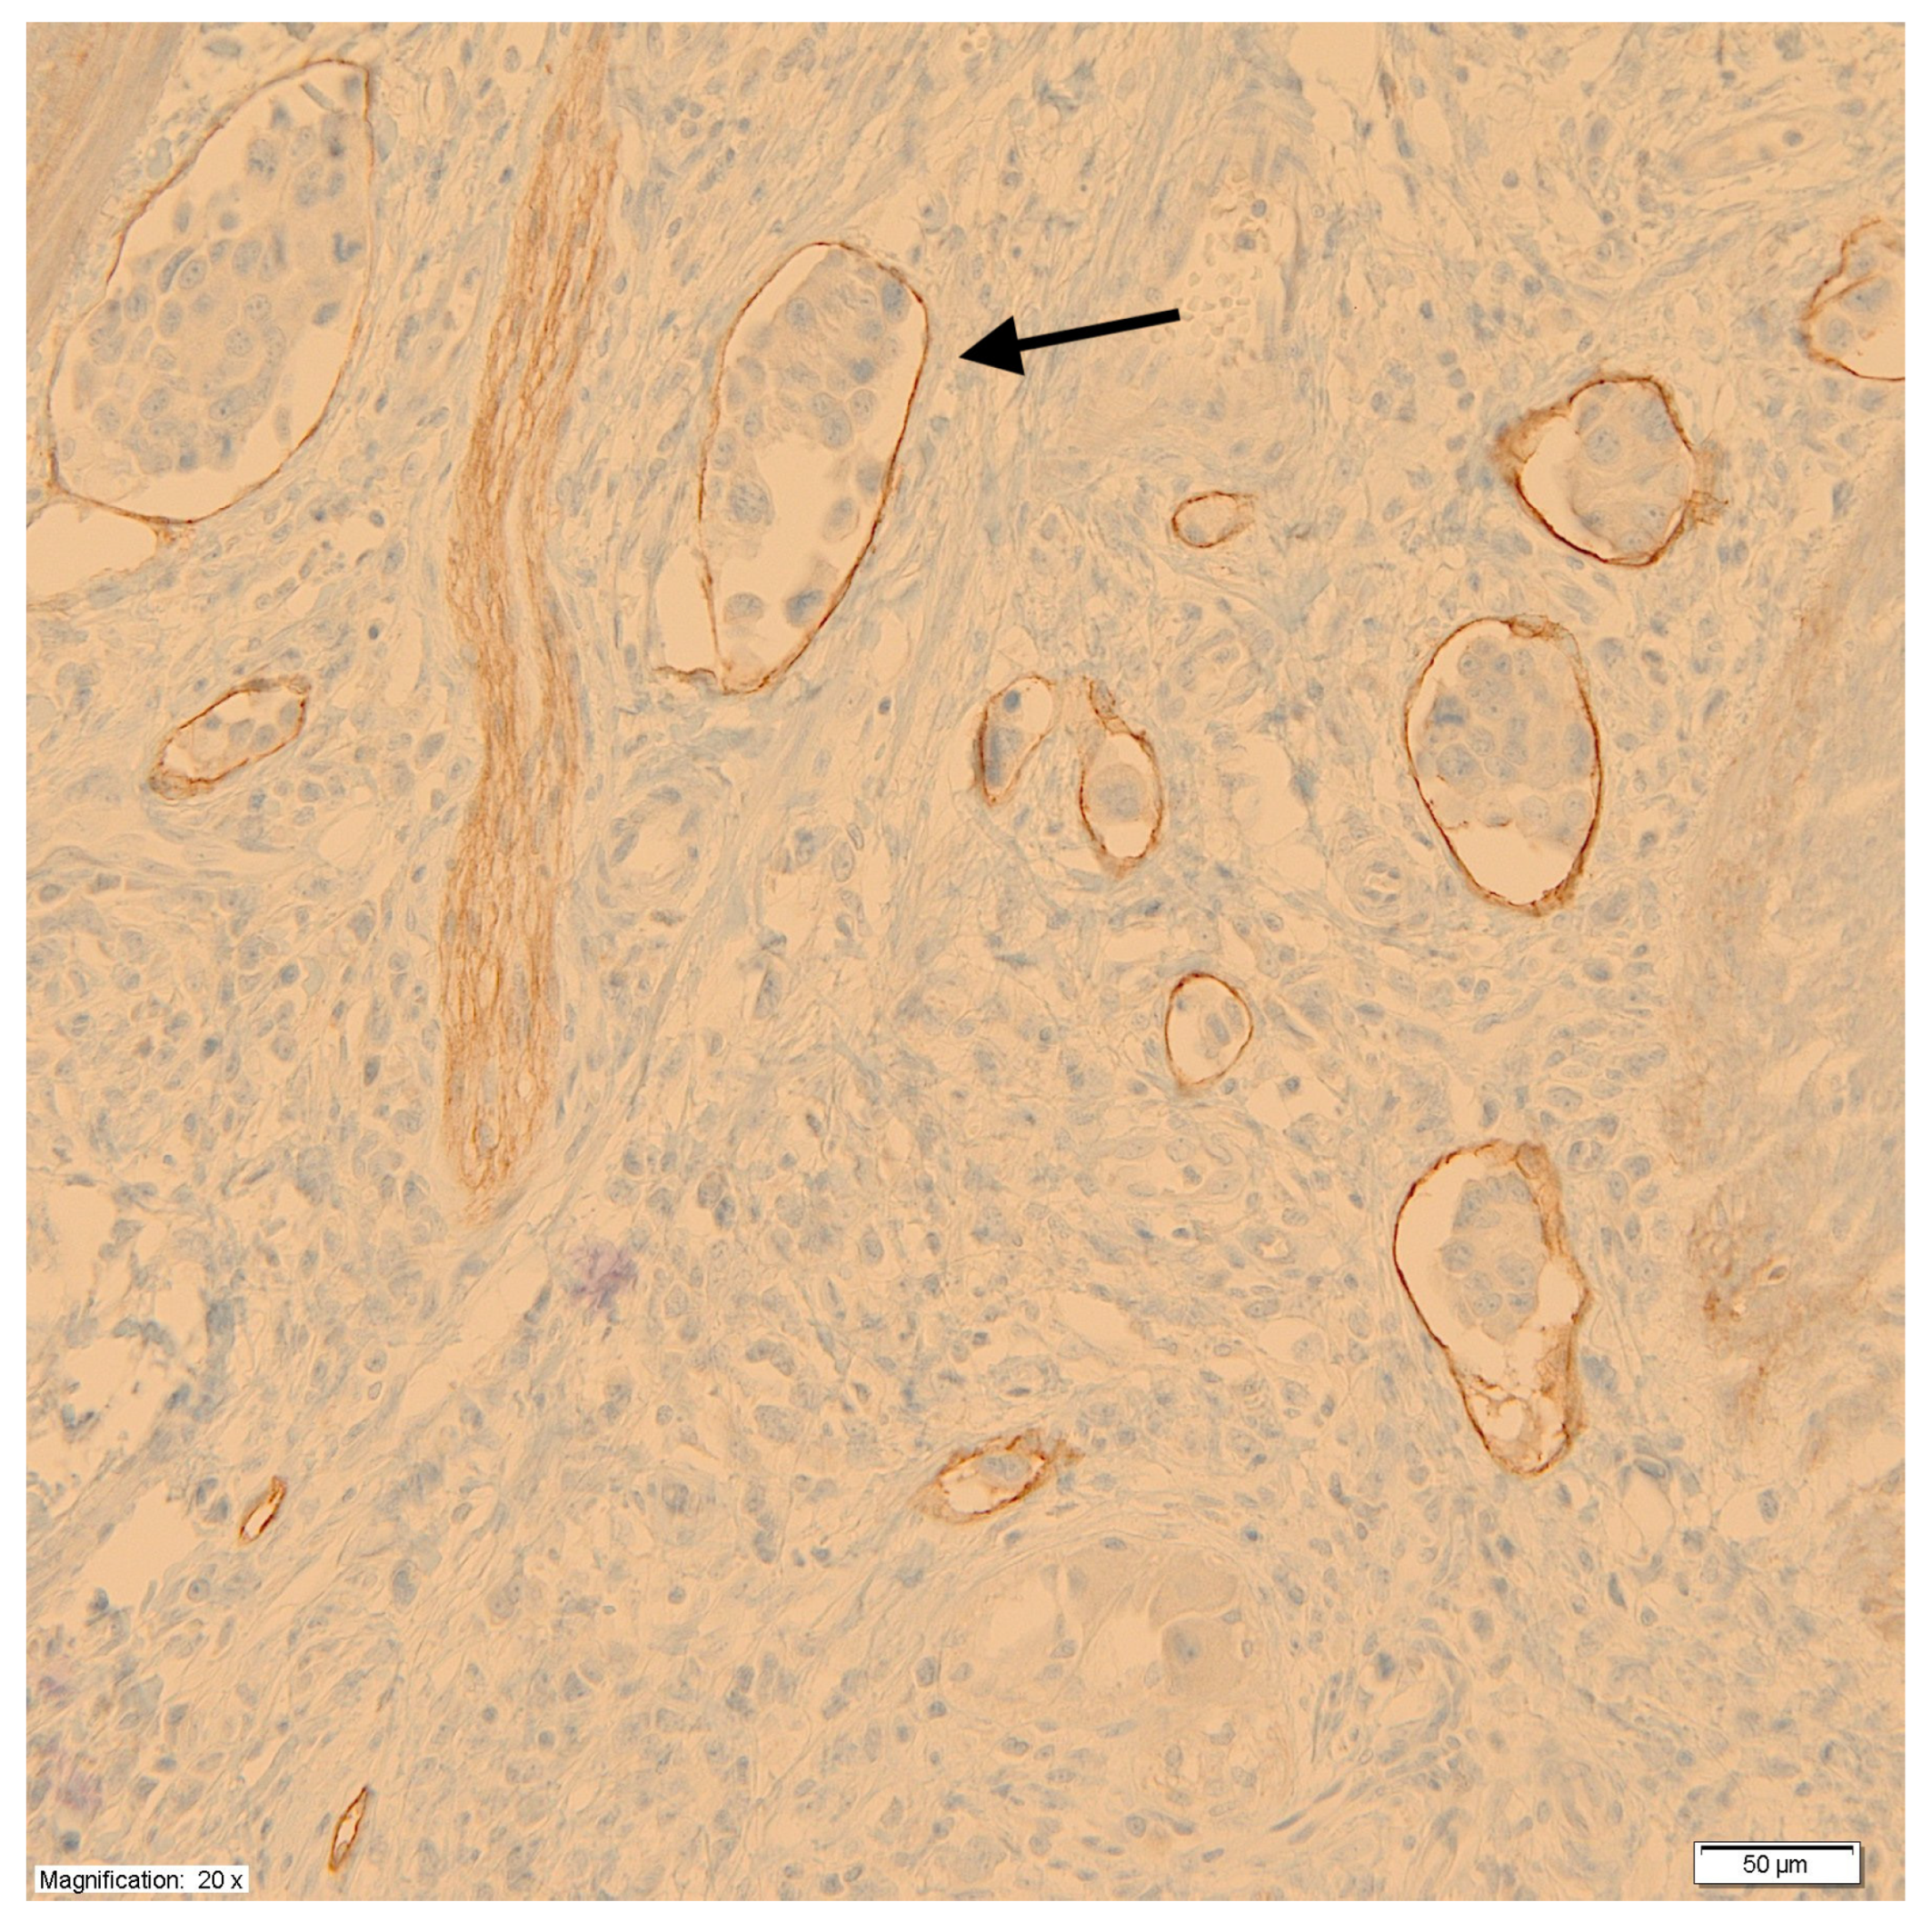

Using monoclonal antibodies against podoplanin (D2-40), the peritumoral LVD was measured at the junction of the tumor and healthy tissue according to the methods of Weidner et al. [28]. First, under low microscope magnification (×100), areas with a high density of lymphatic vessels, so-called hot spots, were identified. Then, in the hot spots, under high microscope magnification (×200), the lymphatic vessels were counted, taking the average value of the measurements at three points as a measure of LVD. Each cluster of endothelial cells or individual vessel was regarded as a hot spot and counted as one microvessel. For the purpose of assessing the impact of LVD on prognosis, tumors were divided into two groups based on median vessel density. Figure 2 shows a microscopic image of labeled lymphatic vessels with the presence of tumor cell emboli.

Figure 2.

Labeled lymphatic vessels with the presence of tumor cell emboli (black arrow).